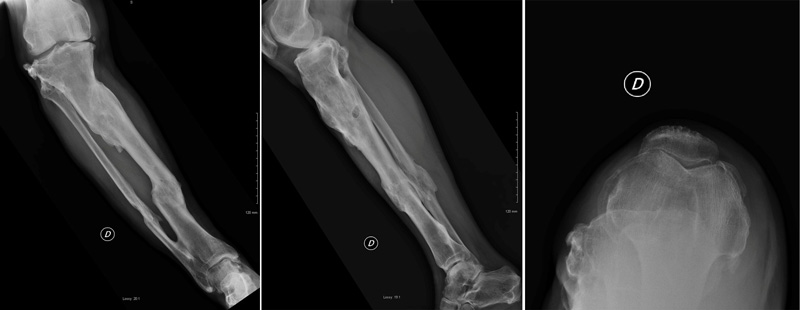

Final strategy decision

A Patient-specific cutting guide on tibial side and a hinged knee prosthesis were used (ADLER ORTHO CUSTOM MADE). Intraoperative tissue sampling was done and an empirical antibiotic therapy was applied before the bacteriological samples came back negative.

Management-of-Total-Knee-Arthroplasty-in-Post-Traumatic-Malunion-figure3

Management-of-Total-Knee-Arthroplasty-in-Post-Traumatic-Malunion-figure4

Management-of-Total-Knee-Arthroplasty-in-Post-Traumatic-Malunion-figure5

Management-of-Total-Knee-Arthroplasty-in-Post-Traumatic-Malunion-figure6